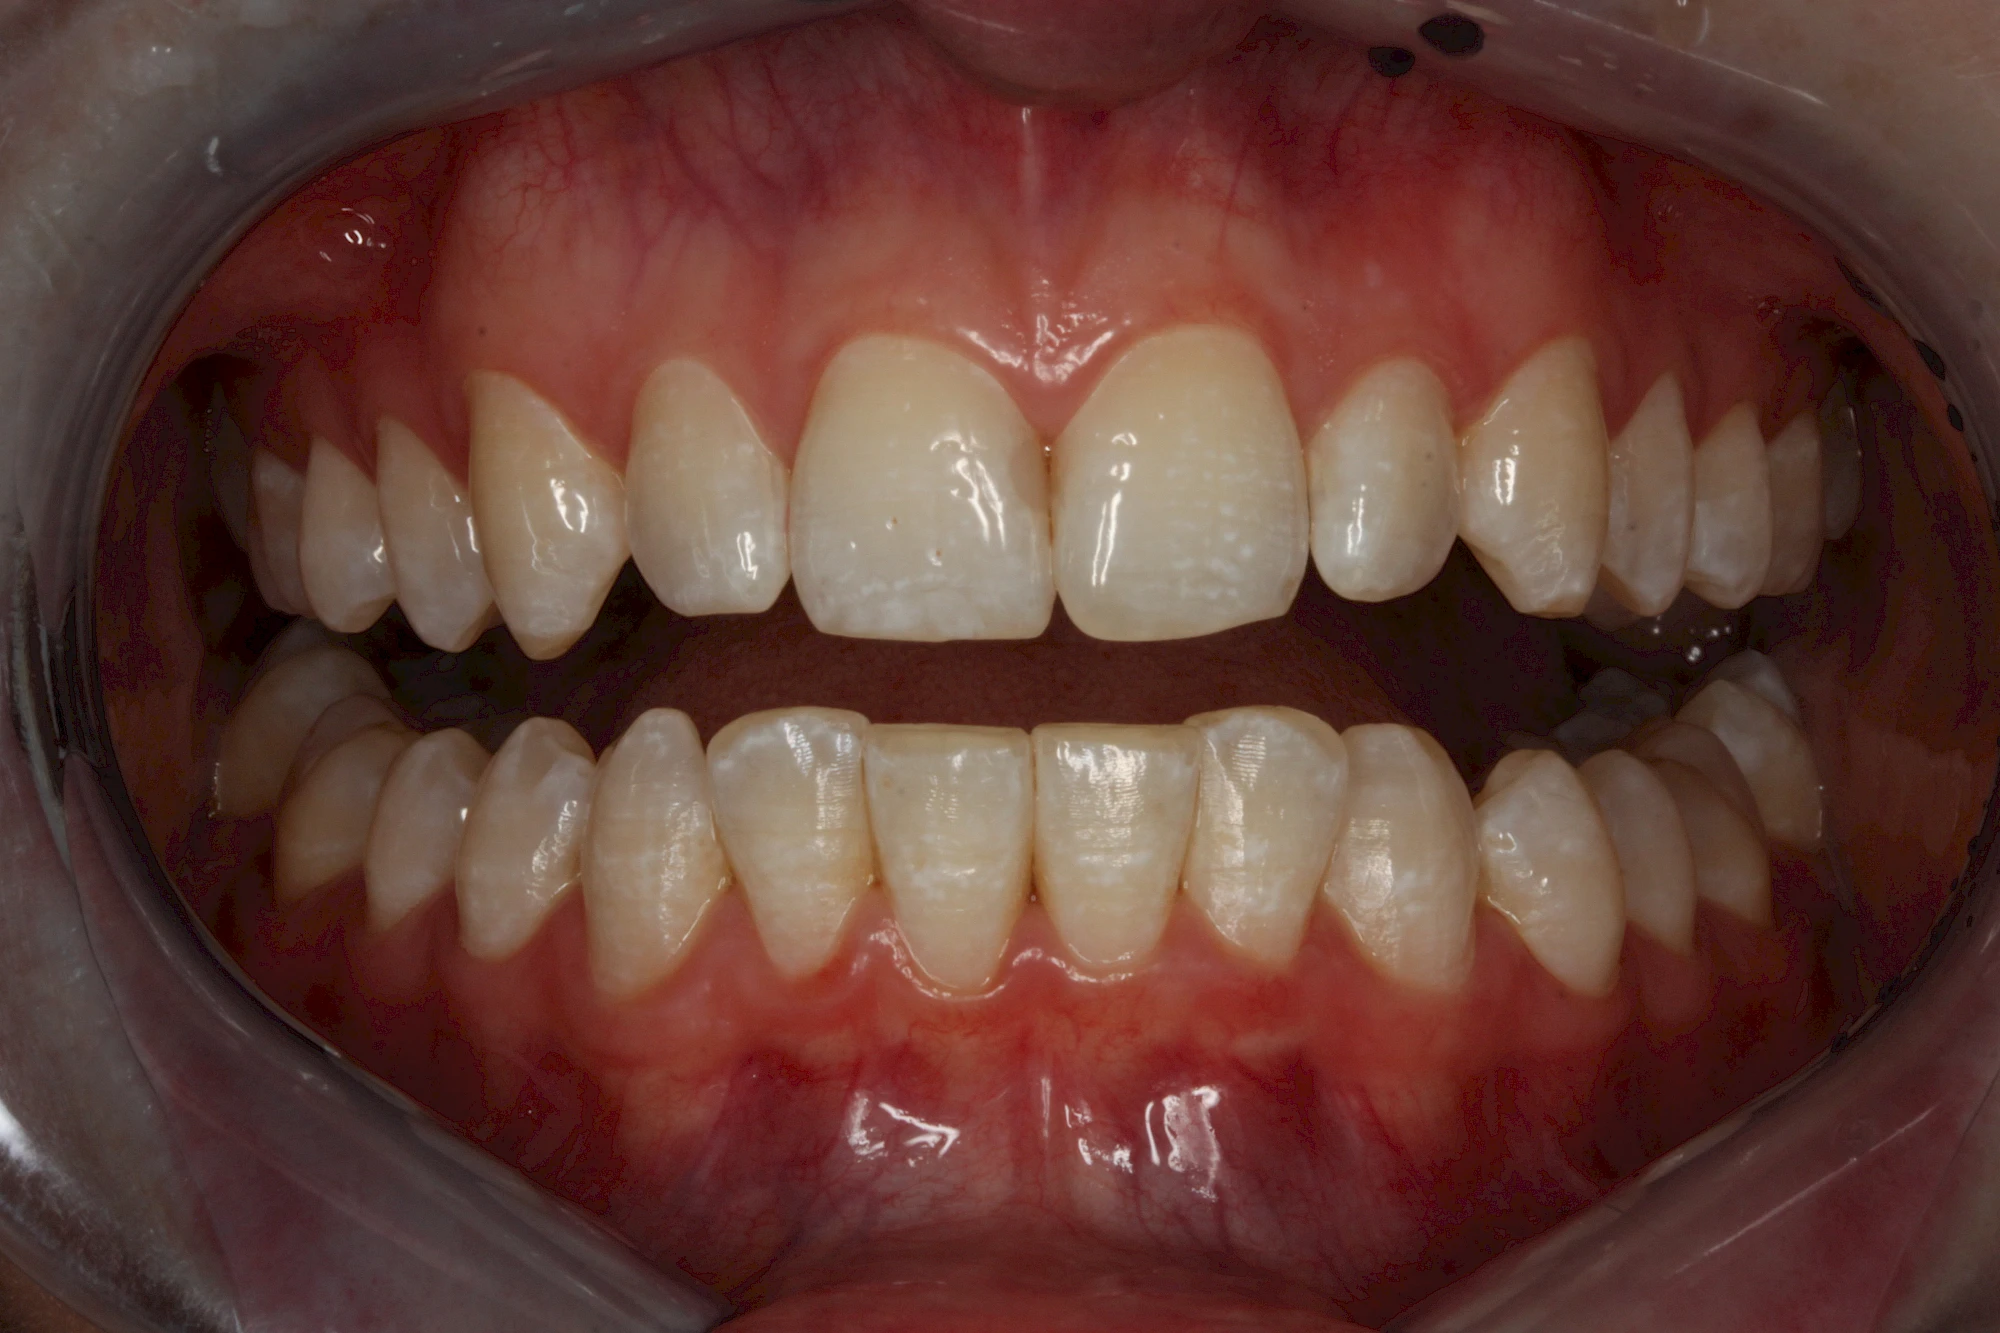

Äußere Verfärbungen durch Genußmittel oder Medikamente (Eisen!) lassen sich meist nur durch den Zahnarzt z. B. mit einer professionellen Zahnreinigung entfernen.

Daneben gibt es noch seltene genetisch bedingte Schmelz- bzw. Dentinbildungsstörungen (Amelogenesis imperfecta, Dentinogenesis imperfecta), die neben Verfärbungen vor allem auch durch Veränderungen der Oberflächenstrukturen auffallen. In diesen Fällen ist eine engmaschige Betreuung durch den Zahnarzt wichtig.